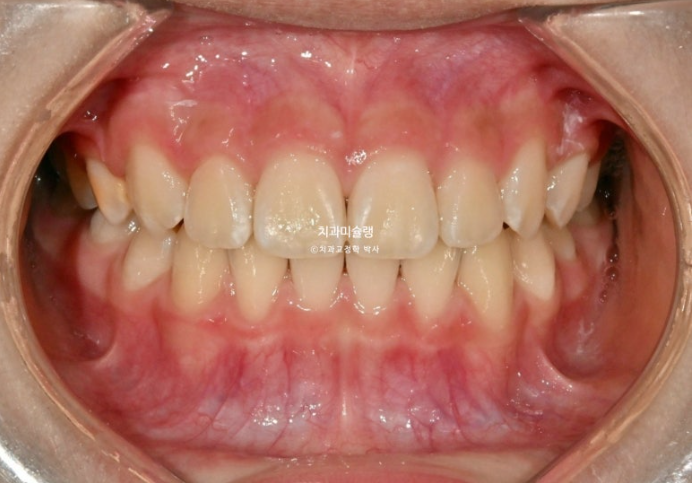

25.11

중심선은 잘 맞고

유치 한 개 빼고 나머지 치아들은 전부 영구치로, 교합이 거의 완성되었습니다.

결과가 성인교정 2차교정에 준하는 만큼 유지장치도 성인과 똑같이 들어갑니다.

파란화살표는 마지막 남은 유치입니다.

이 유치마저 빠지고 모든 영구치가 올라오면 비베라 제작에 들어갈 예정입니다.

과개교합과 중심선 불일치의 개선

완성된 교합은 1급 교합관계를 보입니다.

나중에 성인이 되어 2차교정을 안해도 될 정도의 완성도 입니다.